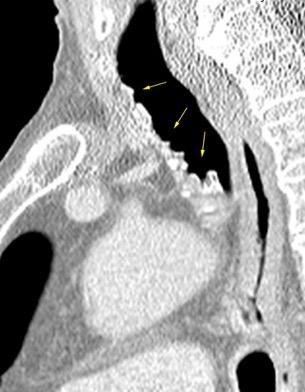

Grupos:

1. Obstrucción por encima de la V Ácigos. (La sangre llega al corazón a través de ella)

2. Obstrucción con participación de la V. Ácigos. (La sangre utiliza otras alternativas para llegar al corazón vía VCI).

Participación de la V. Ácigos como vía principal para llegar a la VCI.

Visible: 88%